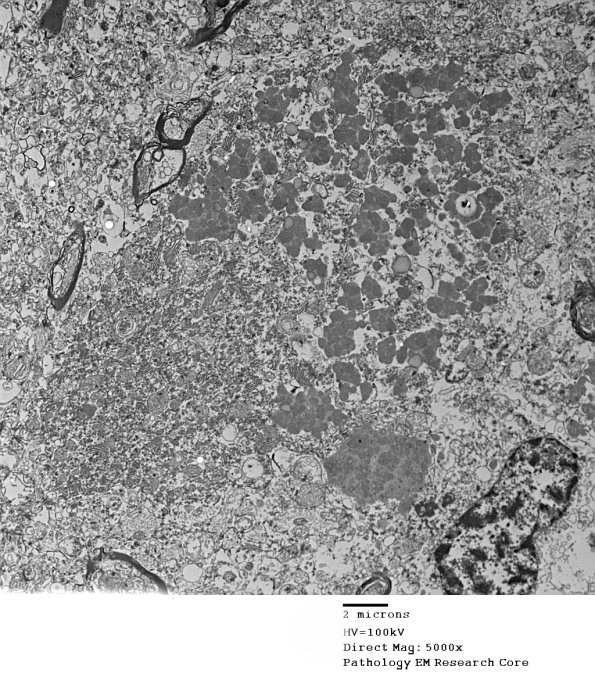

1F1E,F This Purkinje neuron contains lipopigment which appears to be composed of smaller spherical osmiophilic material and lipid. (electron micrographs)